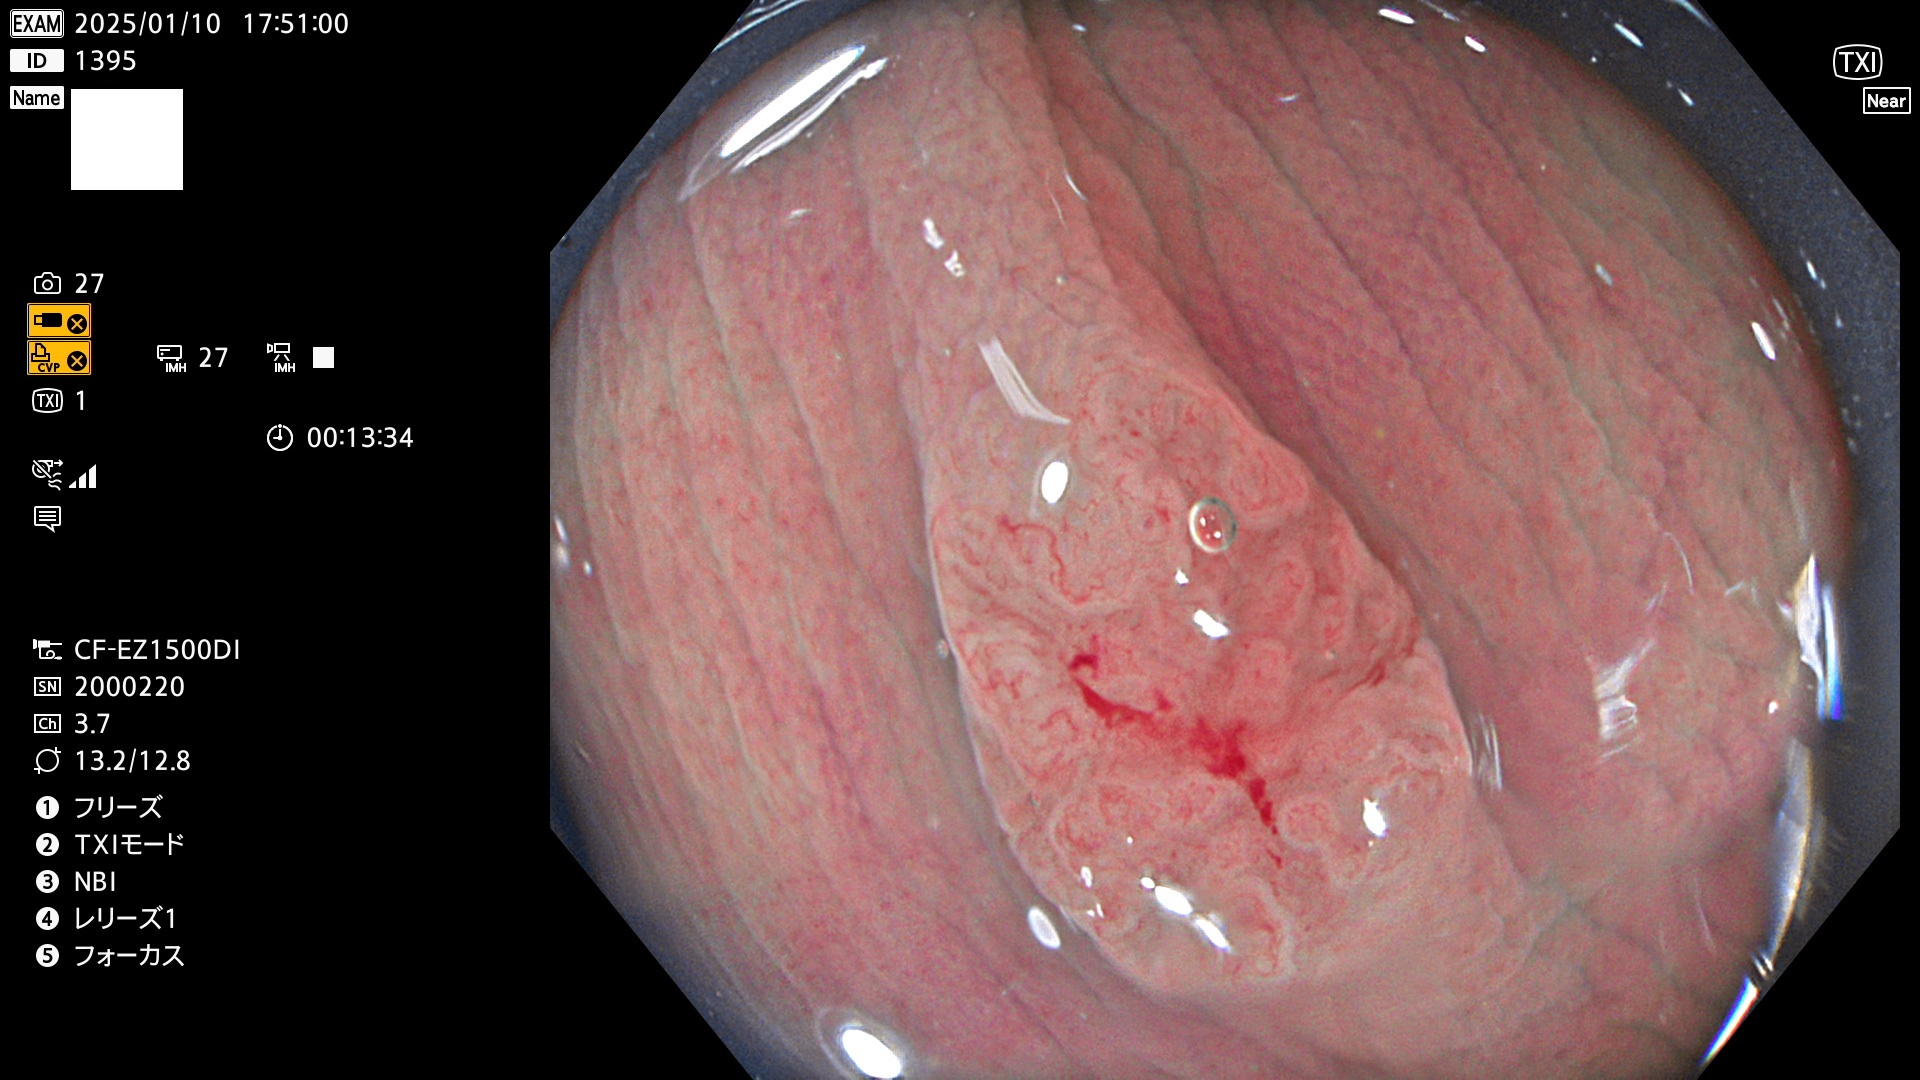

完全に平坦な物をUb、陥凹している物をUcと呼びます。最も発見が難しく危険な病変です。

毎週の検査(木・金・土・日)に発見されたUb、Uc型・腺腫を、その週の日曜の夜にUPし1週間、提示します。

抽出の対象期間 2025年1月9日〜1月12日の4日間(45件の検査)5件 (5/45=11%)